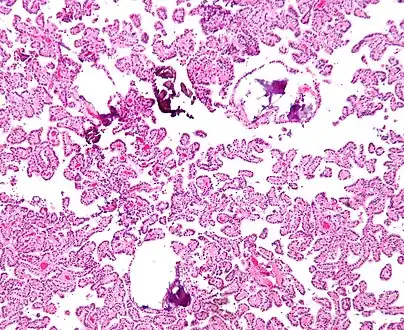

The tumor is neuroectodermal in origin and similar in structure to a normal choroid plexus. They may be created by epithelial cells of the choroid plexus.

Micrograph of a choroid plexus papilloma. H&E stain.

Plexuspapillom Detail